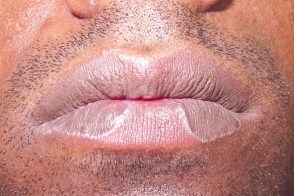

Фото Красного Плоского

Фото Красного Плоского 103 фото